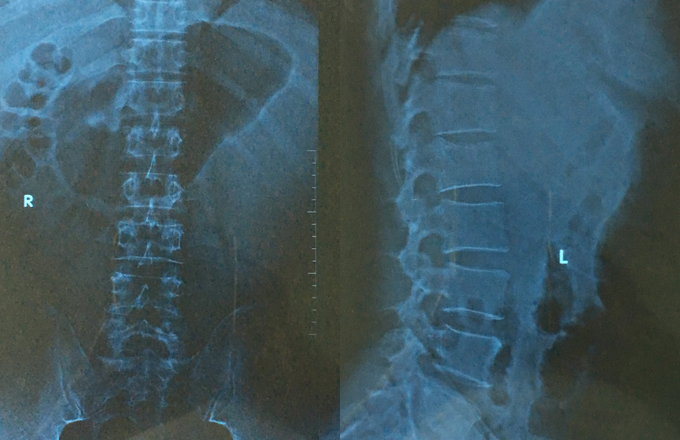

图3:2018年12月28日(41天后)X光复查片

以气运身,滋养机体,太极拳是养生强身的天然运动。有着卧床练功的快乐,在近两个月的卧床生活中,不断坚持静功与动功相结合训练,前期坚持晨练静卧无极桩,白天平躺滚腰及以意练拳,即躺着盘拳,以意念带动手脚运动(如图4)。中期坚持坐靠或叭着练功(如图5),后期跪床练功(如图6)。随着练功深入,腰伤日见好转。期间,有的拳友来访慰问与交流,还兴趣地在床前搭手试劲,内力仍不减。腰伤41天X光拍片复查,腰1骨伤已愈合,诊断为“腰1陈旧性骨折”(如图3),让骨科主任感到惊讶,多次问“是否拿错片”,说“比年轻人恢复还快”。